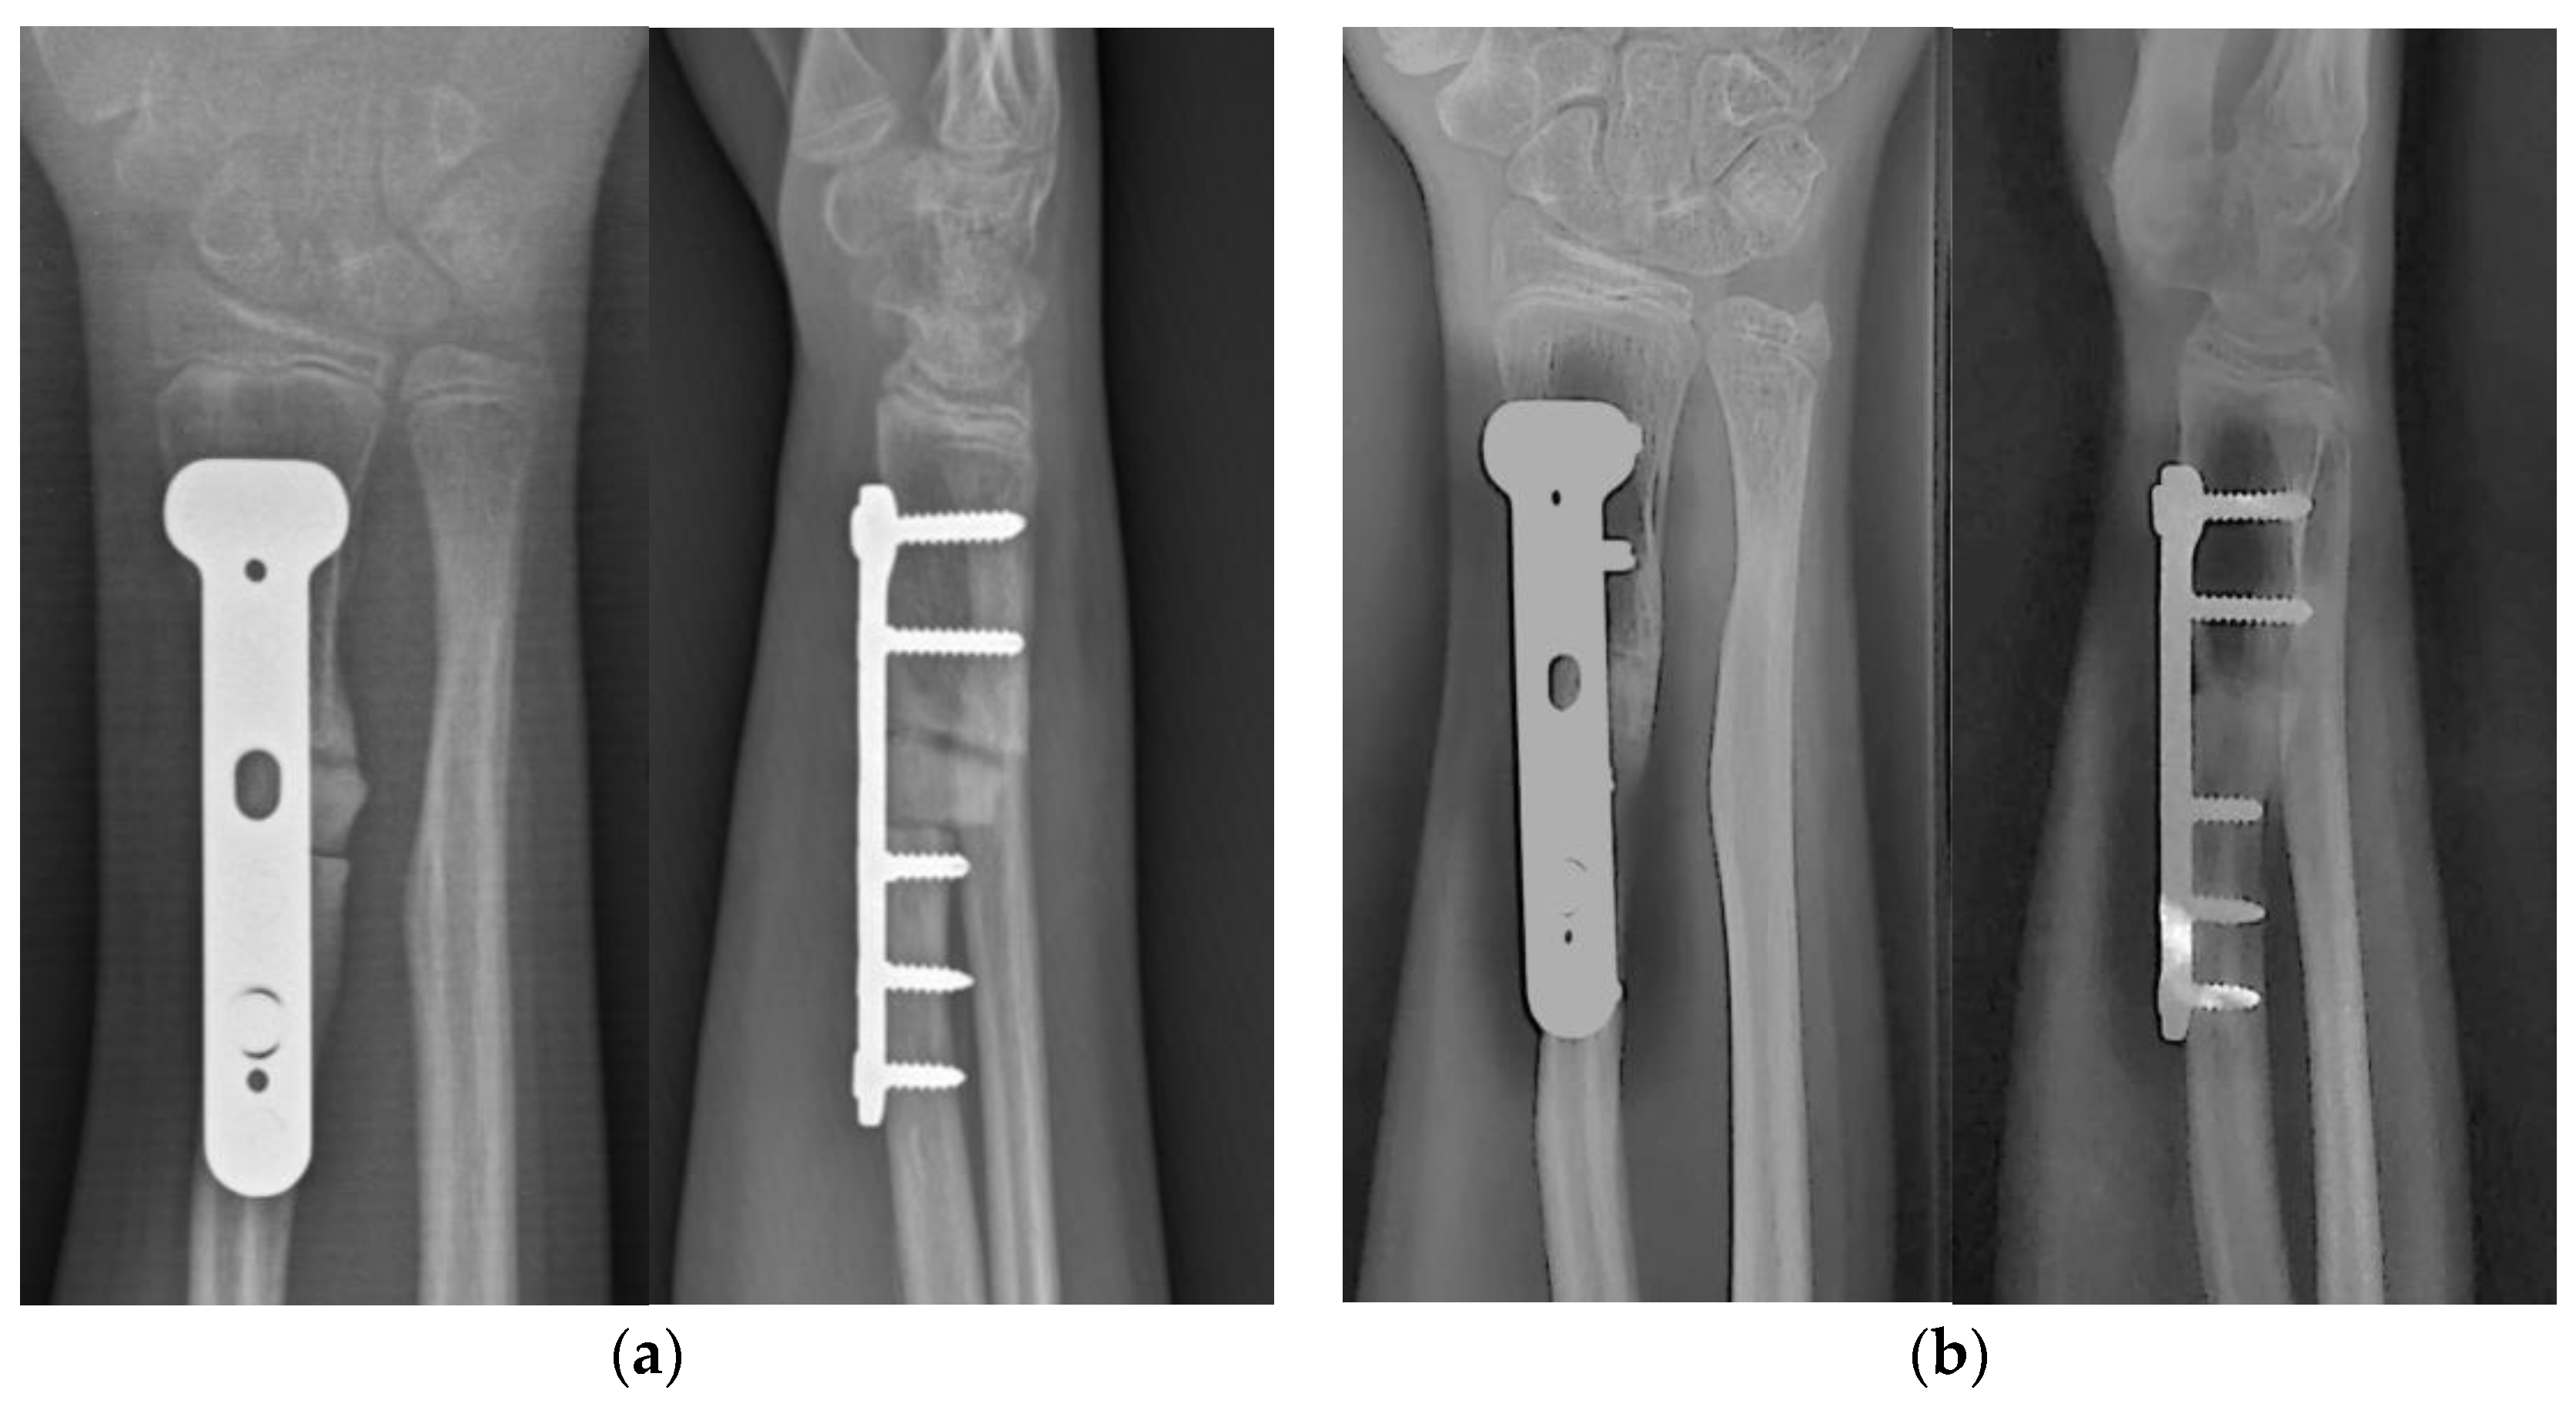

2.1. Case Presentation

2.4. Surgical Treatment

3. Results